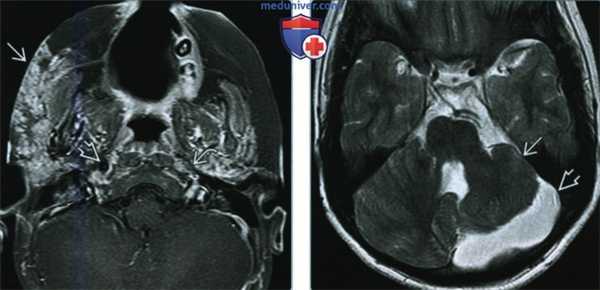

(Слева) При аксиальной МРТ Т1 ВИ С+ FS визуализируется контрастирующаяся гемангиома лица справа с поражением кожи и подкожной клетчатки. Определяется потоковое выпадение сигнала во внутреннем слуховом канале (ВСК) справа (норма). Слева потоковое выпадение сигнала отсутствует в результате атрезии ВСК.

(Справа) При аксиальной MPT Т2 ВИ у этого же пациента определяется гипоплазия мозжечка и мальформация его коры с расширением замозжечкового ликворного пространства. Мост с вентральной стороны уплощен и уменьшен в размерах.

• Пролиферативная гемангиома: дольчатое образование с промежуточным сигналом на МРТ Т2 ВИ , явное потоковое выпадение сигнала, интенсивное контрастирование

• Инволютивная гемангиома: меньший размер, менее очевидное потоковое выпадение сигнала, большое количество фиброзно-жировой ткани, менее интенсивное контрастирование

о Гипоплазия мозжечка ± мальформация (одно- > двухсторонняя) и расширение замозжечкового ликворного пространства